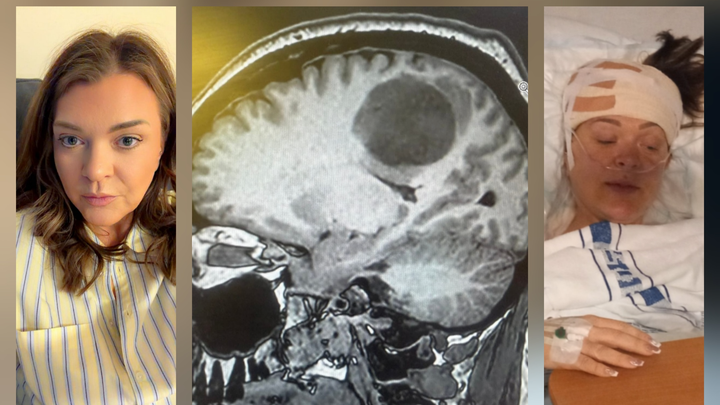

Hi, I’m Sara, one of Emma’s close friends. We are fundraising for our dear friend, who has recently been diagnosed with a brain tumour. She has had surgery to reduce it, but unfortunately it’s not something that can be removed or fixed due to its size and location. Since the operation, Emma has lost movement and sensation down her left side, so she now needs a lot more support day-to-day (and yes, her friends will be wheeling her about — whether she likes it or not).

Over the past year she has been going to the doctors with symptoms — pins and needles in her head, her left foot, strange sensations — and was told it was menopause and put on HRT. Last week things changed. She started losing feeling down her left-hand side, so took myself to the doctors. They sent her straight to hospital, and on Friday 13th March, after one scans, she was given news that completely turned her world upside down.

She has a brain tumour!!!!

It’s large, deep, and on the right side of her brain — which is affecting her left side. On the 17th March she had the conversation no one ever wants to have. That the tumour isn’t fully fixable. But they are going to operate to remove what they can, and do everything possible to give her the best quality of life moving forward. On the 18th March she had this operation where they discovered the worst news ever...she has two to six months to live, and to go and enjoy what time she has left.

However, things have progressed faster and by the next day Emma has no movement or feeling in her left leg and only small amount of movement in her left arm.

This diagnosis has turned Emma’s world upside down in a matter of weeks. She has already been through a horrific operation, countless appointments, scans, and difficult conversations with doctors, and is now, in hospital, focusing on comfort, time with loved ones, and making as many special memories as she can in the time she has left. She is facing all of this with incredible courage, but she cannot and should not have to do it alone.